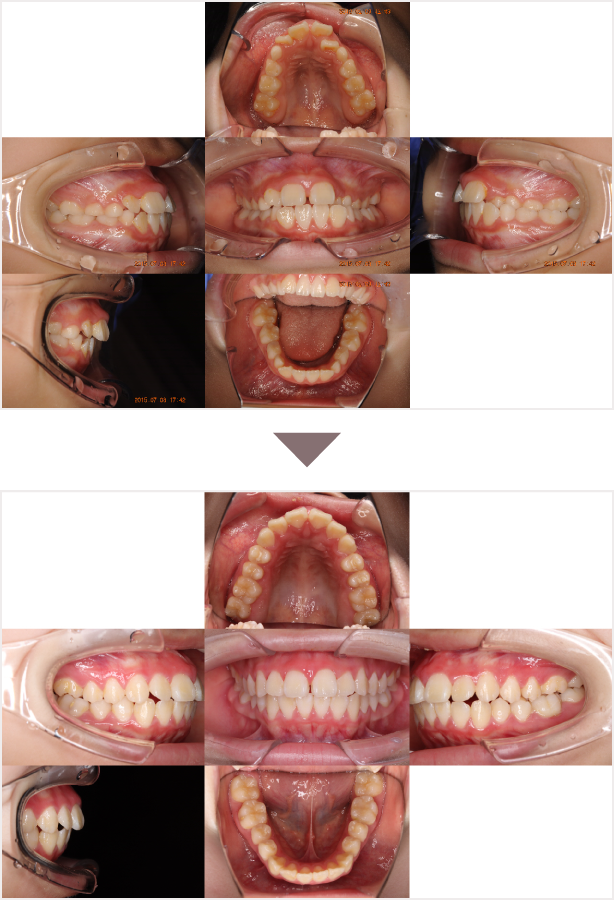

症例叢生

性別

期間6年5ヶ月

治療内容N-Bimler装置、Neo-Capを使用して治療

治療における

副作用・リスク

装着しないと効果は出ません

金額ビムラー装置:550,000円

ネオキャップ:4本

合計:572,000円